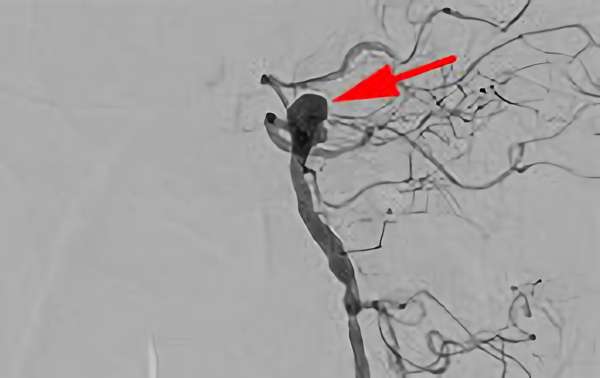

No.1628 手術前